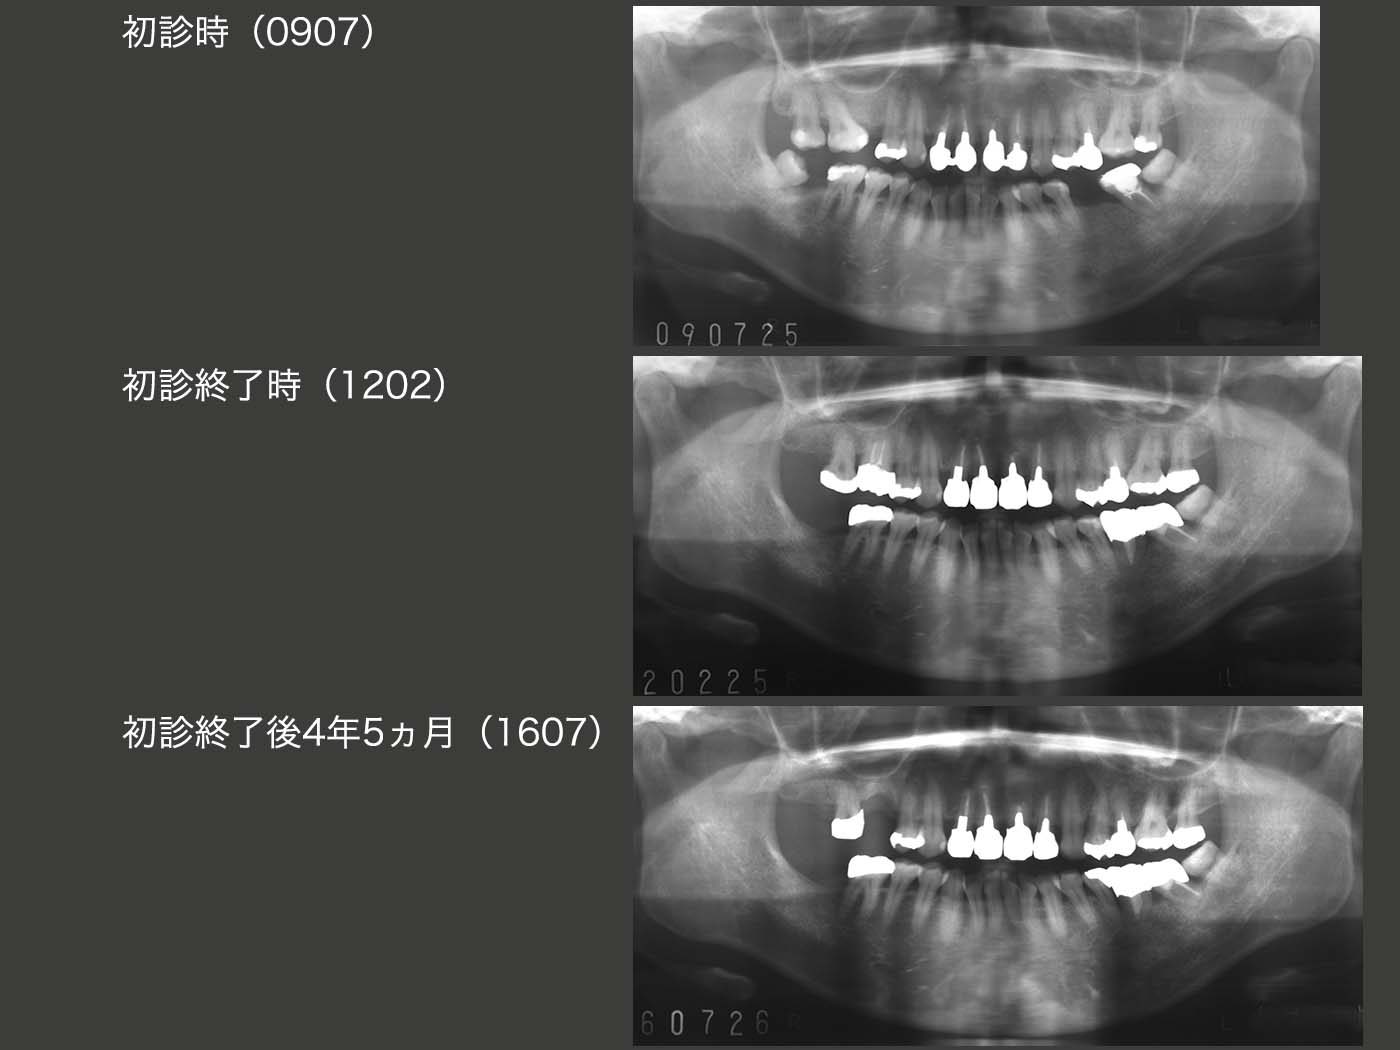

各ステージのパノラマX線写真の比較.苦労して移植した右上5(元右下8)を失ったのは大変残念である.抜歯窩でなく,顎堤への移植は難しいと改めて思い知らされた.結果的には,右下8の移植を行わず,最初から可撤式ブリッジを装着すれば良かったことになるが後の祭りである.

2009年7月初診,38歳女性.右上および左下の欠損の治療ならびに前歯の隙間が気になるという主訴で来院.上顎前歯は10年前イタリア留学中に製作したとのこと.全体に軽度の歯周病がみられた.特に左下7の遠心に10mmの歯周ポケットあり,この結果左下⑤6⑦のブリッジは難しいと判断した.

ところが,初診終了後2年5ヵ月(2014年7月)の定期健診の時に,右上5(移植歯)の舌側に歯周ポケットが認められた.その原因は根尖病巣あるいは歯根膜による付着が得られなかったことによる歯周病が考えられるが,取り敢えず冠を外し,感染根管治療を行った.しかし1年経過しても,歯周ポケットは回復せず,抜歯せざるを得ない状況に陥った.09年にアップライトしたため,右上6は対合歯と少ししか咬合していなかった.今度は,できれば近心に移動させて,右下6ともっと咬合させたかった.(ちぐはぐな治療を行ってしまった)移植歯はまったく動揺せず,骨と癒着していたため,最後のご奉公として移植歯を半分にカットし,歯科矯正の固定源として利用した.なお補綴装置は,右上4を切削したくなかったので固定性のブリッジとはせず,可撤式のブリッジ(コーヌス義歯)とした.

2018年4月,移植歯である左下6(元右上7)の動揺が大きくなった.歯周ポケットは遠心で5mm存在した.このままではさらに動揺が大きくなり,保存が危ぶまれると判断し,左下7と連結固定することにした.(結果的には,最初から連結固定したほうが良かったということなるが.)